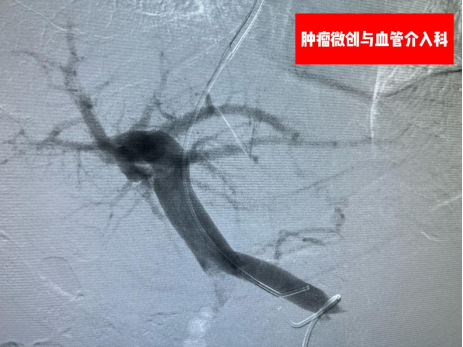

据徐兴鲁主任介绍,TIPS手术最大的优势在于微创,通常经颈静脉途径穿刺,通过在肝静脉与门静脉之间的肝实质内建立分流道,以微创的方式从结构上显著降低门静脉阻力。该手术广泛应用于肝硬化门静脉高压所致的食管胃静脉曲张破裂出血、顽固性胸腹水、肝窦阻塞综合征、门静脉血栓等疾病治疗,对部分急危患者能起到立竿见影的效果。科室曾采用该技术救治过一名49岁男性消化道大出血病人,术前患者门静脉高压并发食管胃底静脉曲张,到达医院急诊科时已经休克,生命垂危,急需采取经颈静脉门腔分流术(TIPS)救治。在征得患者家属同意后,徐兴鲁团队在急诊科、麻醉科、手术室医护人员的配合下,连夜在最短的时间内成功为病人“搭桥”,在门静脉与肝静脉之间植入一枚8í80mm的覆膜支架,门静脉血流引流回到下腔静脉,压力下降,出血停止,患者生命得以挽救。看着醒来的患者,病人家属激动的无以言表。